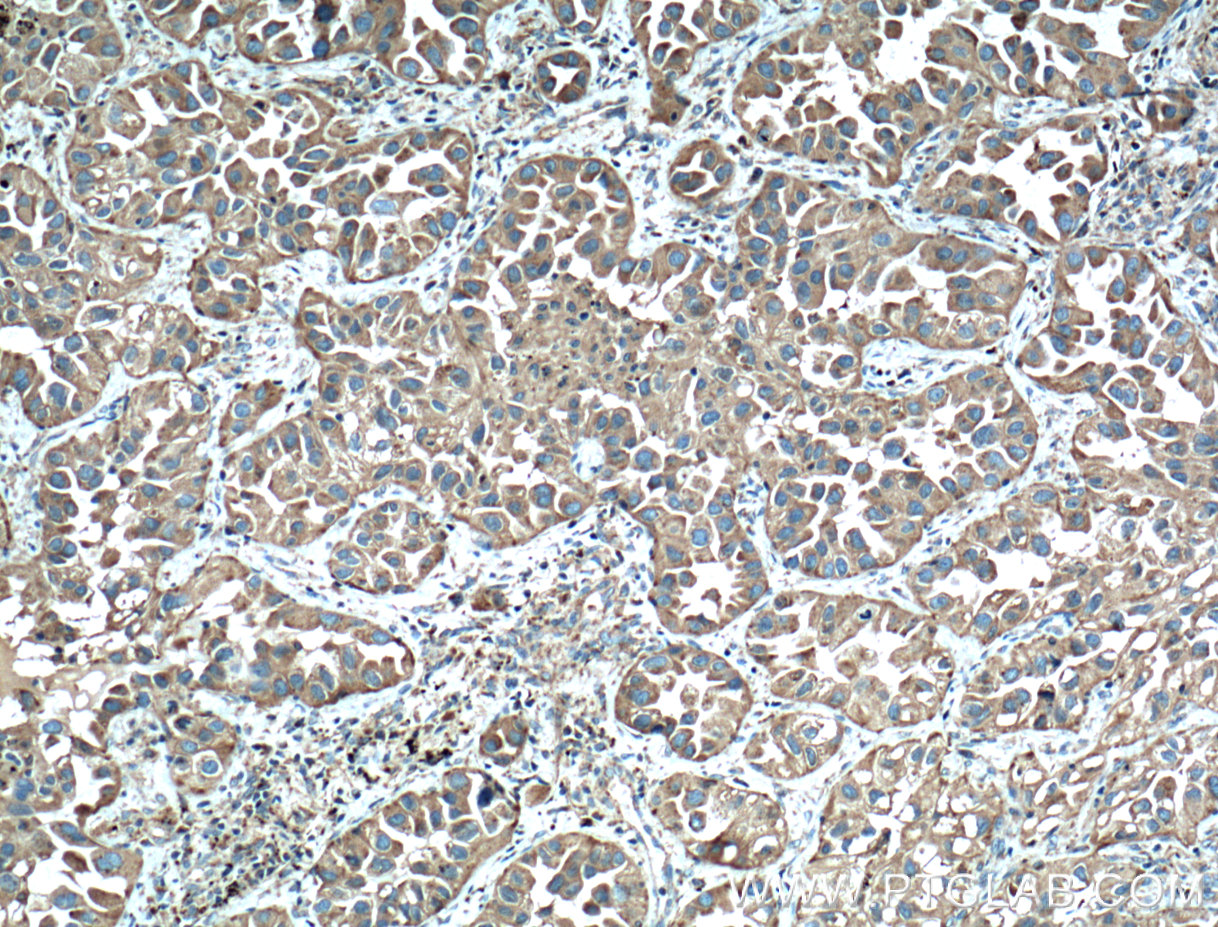

| Positive IHC detected in | human liver cancer tissue, mouse liver tissue, human lung cancer tissue, human liver tissue, human kidney tissue Note: suggested antigen retrieval with TE buffer pH 9.0; (*) Alternatively, antigen retrieval may be performed with citrate buffer pH 6.0 |

| Immunohistochemistry (IHC) | IHC : 1:500-1:2000 |